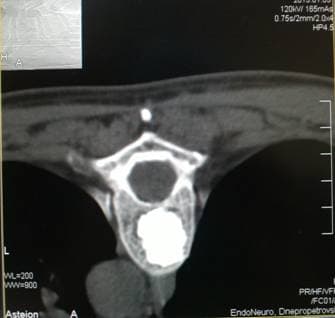

Игла в теле позвонка

Позиционирование иглы в теле позвонка под контролем КТ